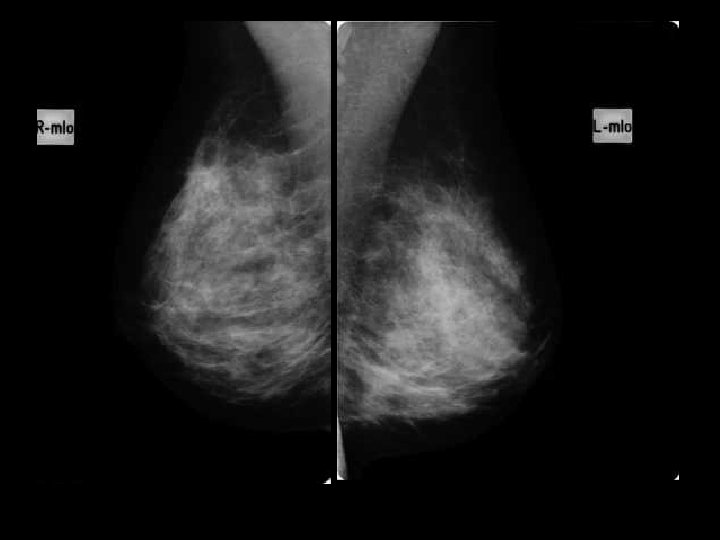

D face ext 46 ans, placard QSE droit de 4 cm palpé par la gynécologue

U Q Sup droits Biopsie : CLI